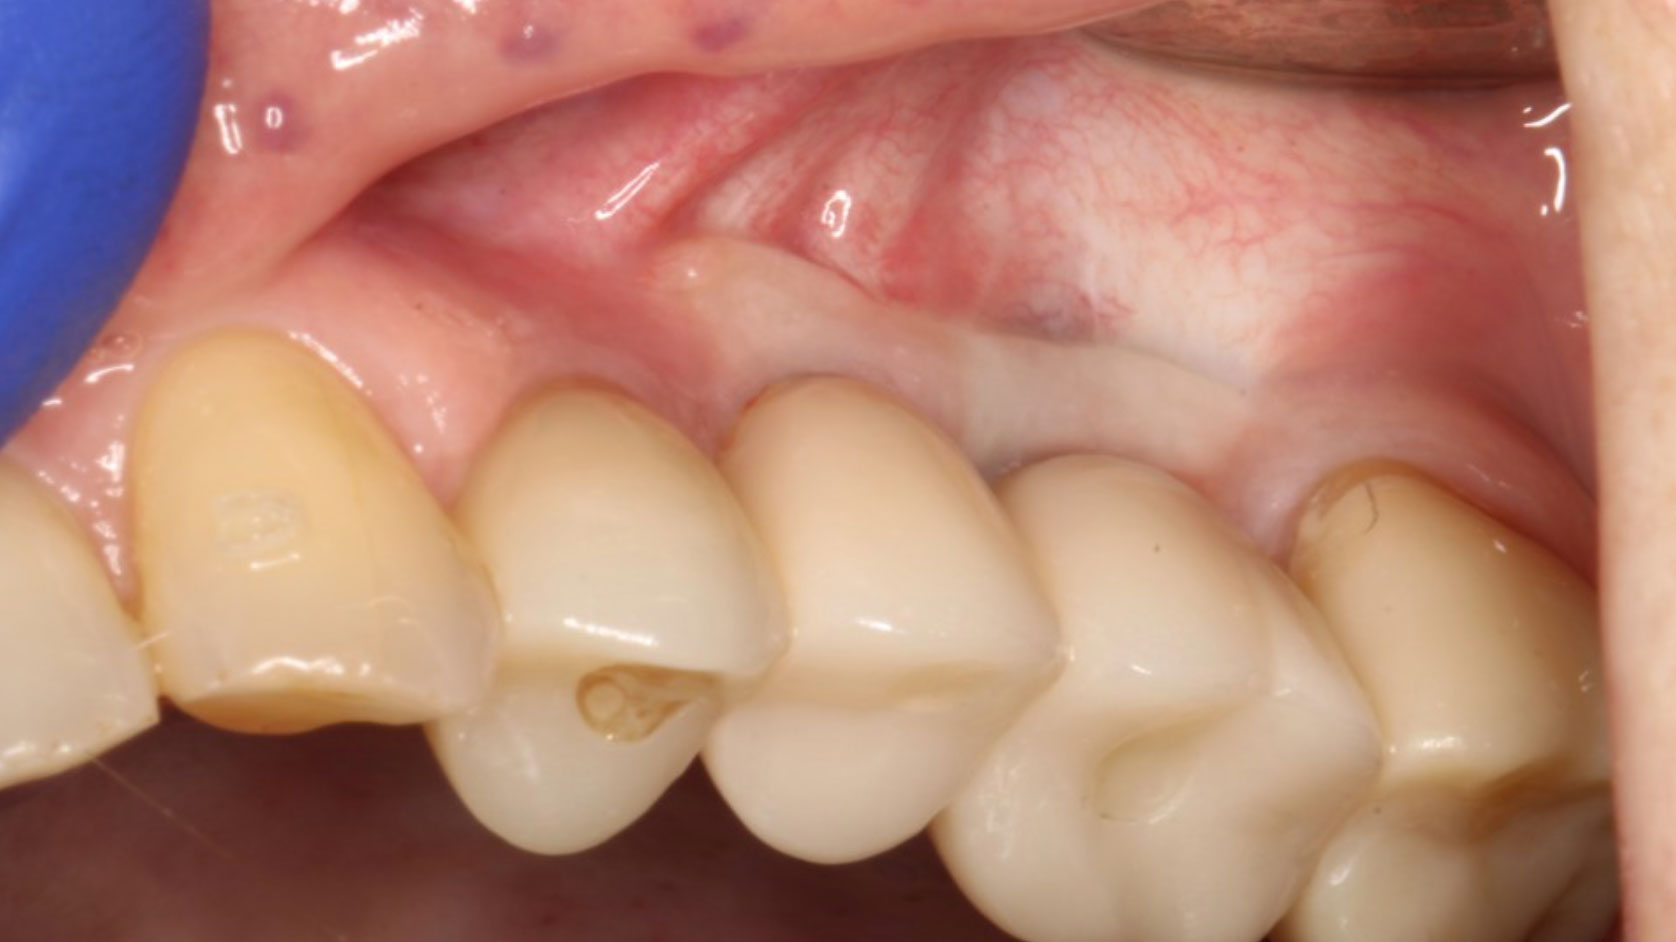

The importance of healthy, thick peri-implant soft tissue: Characteristics, management, and prevention of complications

The quality of peri-implant soft tissue plays a pivotal role in the long-term success of dental implants. Thicker peri-implant mucosa, particularly when accompanied by adequate keratinized mucosa, is associated with enhanced aesthetic outcomes, reduced risk of peri-implant diseases, and improved patient satisfaction. The peri-implant soft tissue complex, encompassing the keratinized mucosa (KM), mucosal thickness (MT), … Read more